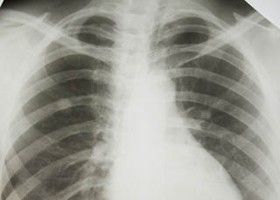

Közel járnak egy "elektronikus orr" kidolgozásához, amely a kilélegzett levegőből képes megállapítani a tbc baktériumával való fertőzöttséget, így az eszköz a tuberkulózis gyors diagnózisát teheti lehetővé - jelentették be hétfőn indiai kutatók.

Tbc, tuberkulózis miatt évente 1,7 millió ember hal meg, a kutatók úgy vélik, az e-orr alkalmazása ebből évente 400 ezer ember életét megmenthetné azáltal, hogy a korai diagnózist követően megfelelő kezelést kaphatnak a páciensek, a fertőzés továbbadásának kockázata pedig mérséklődne. Az Egészségügyi Világszervezet (WHO) becslése szerint egy kezeletlen, aktív tbc-vel élő ember átlagosan 10-15 további embert fertőz meg évente.